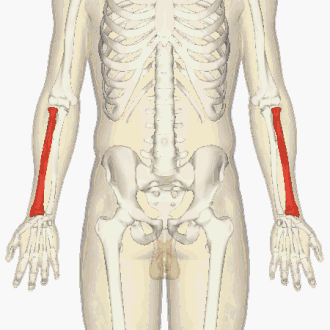

Le radius (du latin, radius, « rayon »), est un os long interne du zeugopode du membre chiridien des vertébrés tétrapodes. Chez l'Homme, le radius constitue, avec l'ulna, l'avant-bras dont il occupe la partie latérale.

Il s'articule au niveau du coude avec l'humérus et l'ulna, et au niveau du poignet avec l'ulna, l'os scaphoïde et l'os lunatum.

L'ulna et le radius jouent un rôle décisif dans le mouvement de pronation / supination de l'avant-bras.

Il est constitué d'un corps (la diaphyse) et de deux extrémités (les épiphyses proximale et distale).